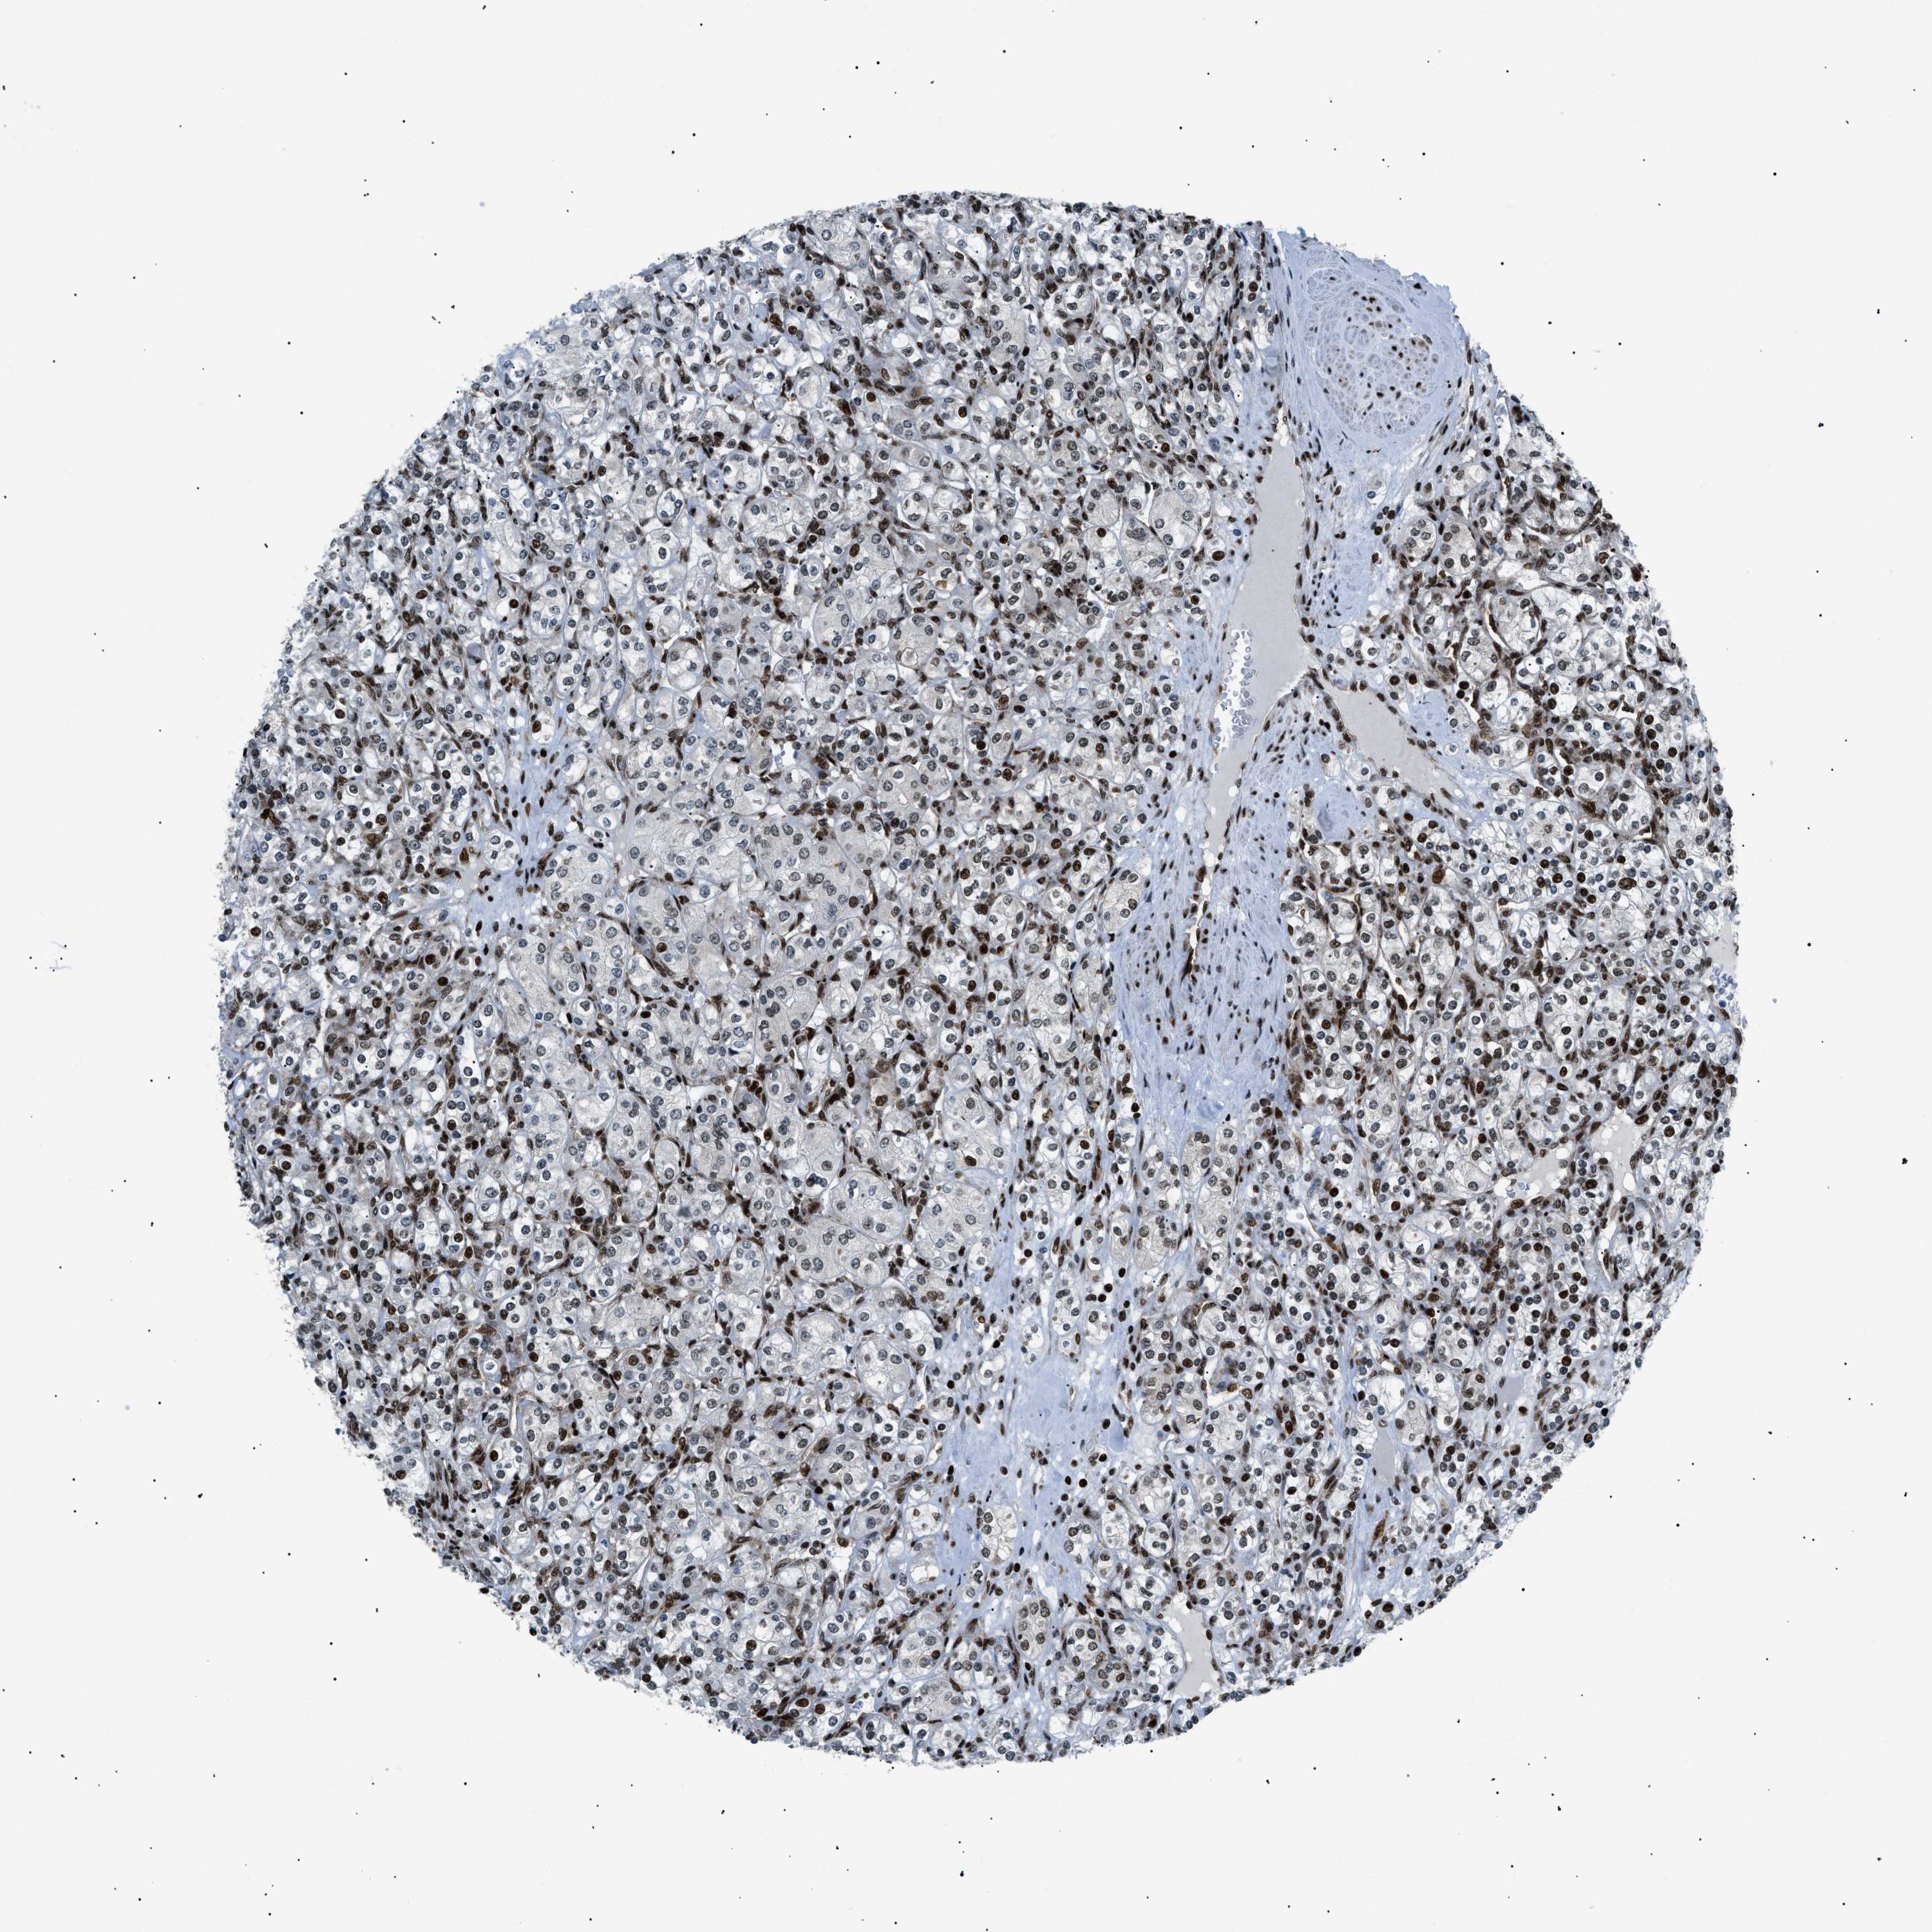

KIDNEY RENAL CLEAR CELL CARCINOMA (VALIDATION) - Interactive survival scatter ploti

The Survival Scatter plot shows the clinical status (i.e. dead or alive) for all individuals in the patient cohort, based on the same data that underlies the corresponding Kaplan-Meier plots. Patients that are alive at last time for follow-up are shown in blue and patients who have died during the study are shown in red.

The x-axis shows the expression levels (FPKM) of the investigated gene in the tumor tissue at the time of diagnosis. The y-axis shows the follow-up time after diagnosis (years). Both axes are complimented with kernel density curves demonstrating the data density over the axes. The top density plot shows the expression levels (FPKM) distribution among dead (red) and alive patients (blue). The right density plot shows the data density of the survived years of dead patients with high and low expression levels respectively, stratified using the cutoff indicated by the vertical dashed line through the Survival Scatter plot. This cutoff is automatically defined based on the FPKM cutoff that minimizes the p-score. The cutoff can be changed by dragging the vertical line or by entering a cutoff value in the square labeled "Current cut-off".

Under the Survival Scatter plot the p-score landscape (black curve; left axis) is shown together with dead median separation (red curve; right axis). Dead median separation is the difference in median mRNA expression between patients who have died with high and low expression, respectively. It is calculated as follows: median FPKM expression of dead patients with high expression - median FPKM expression of dead patients with low expression. This is intended to aid the user in visually exploring custom cutoffs and the associated p-scores and dead median separation.

Individual patient data is displayed and can be filtered by clicking on one or more of the category buttons on the top of the page. Categories describing expression level and patient information include: high, low, alive, dead, female, male and tumor stages. The scale of the x-axis can be toggled between linear and log-scale by clicking on the "x log" button. Mouse-over function shows TCGA ID, patient information and mRNA expression (FPKM) for each patient.

& Survival analysisi

Kaplan-Meier plots summarize results from analysis of correlation between mRNA expression level and patient survival. Patients were divided based on level of expression into one of the two groups "low" (under cut off) or "high" (over cut off). X-axis shows time for survival (years) and y-axis shows the probability of survival, where 1.0 corresponds to 100 percent.

HNRNPK is validated prognostic, high expression is favorable in Kidney Renal Clear Cell Carcinoma (validation)

: 384.93

Average pTPM 408.9

Number of samples 100